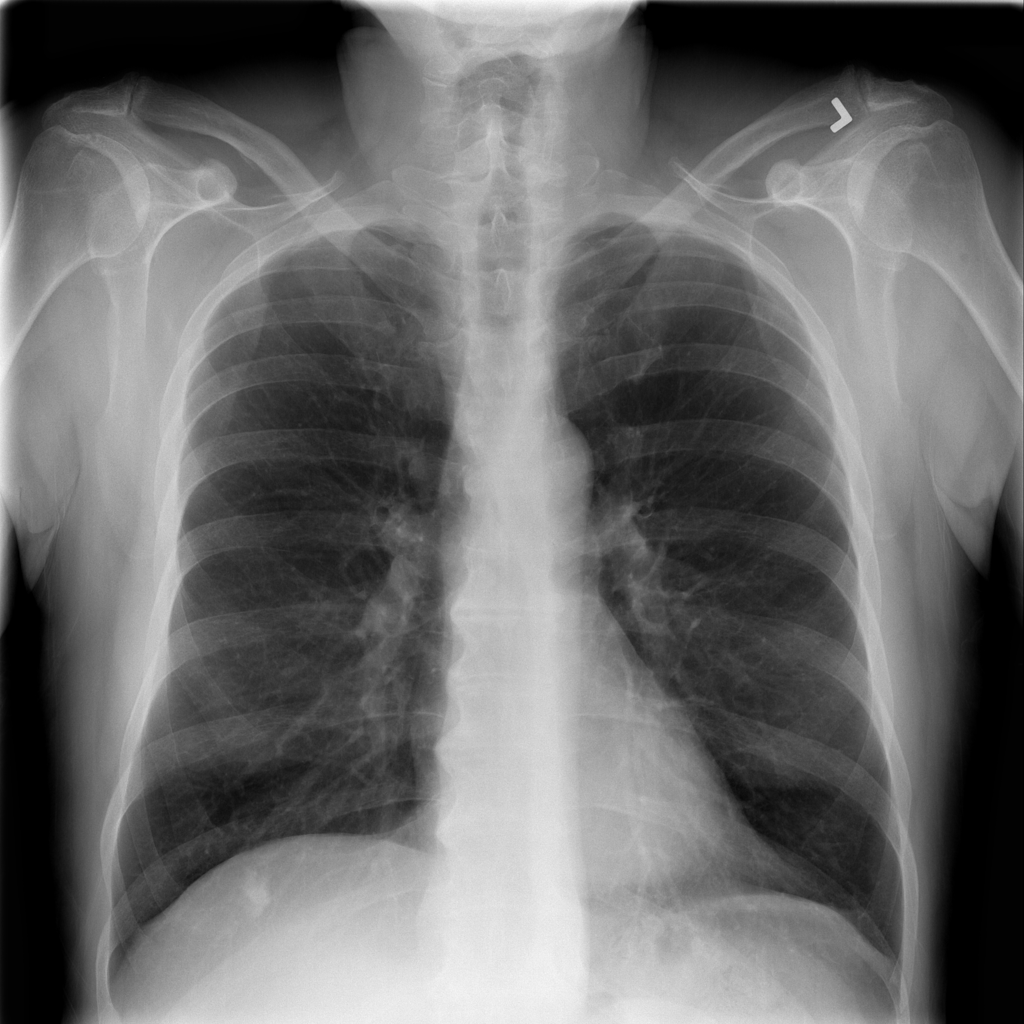

Showing up to 90 reference images for Nodule.

PAT-50E5 · IMG-000Nodule

PAT-50E5 · IMG-000

PA